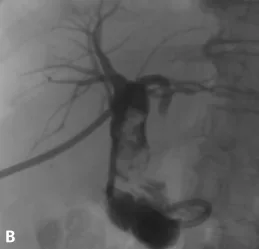

Figure 2.

A. Acquisition 3D de bili-IRM. Chez ce patient à la respiration irrégulière, l’échec de la synchronisation respiratoire (nécessaire à l’acquisition de cette séquence) rend dans ce cas les images quasi ininterprétables.

B. Ici, c’est une coupe épaisse 2D acquise lors d’une courte apnée qui s’avère plus contributive pour montrer l’empierrement cholédocien (têtes de flèches)